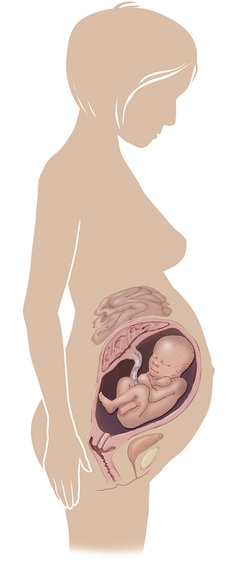

مراحل تطور الجنين أثناء الحمل

تطور الجنين خلال فترة الحمل على ثلاثة مراحل: أول 14 أسبوع من الحمل ، ثم تطوره بداية من الأسبوع 14 وحتى 28 أسبوعا ، ثم الثلث الأخير من 28 إلى 40 أسبوع من الحمل ... المزيد

مراحل تطور الحمل أسبوعيا بالصور

مراحل تطور الحمل أسبوعيا لكل من الأم والجنين داخل الرحم مدعومة بالصور التوضيحية ... المزيد